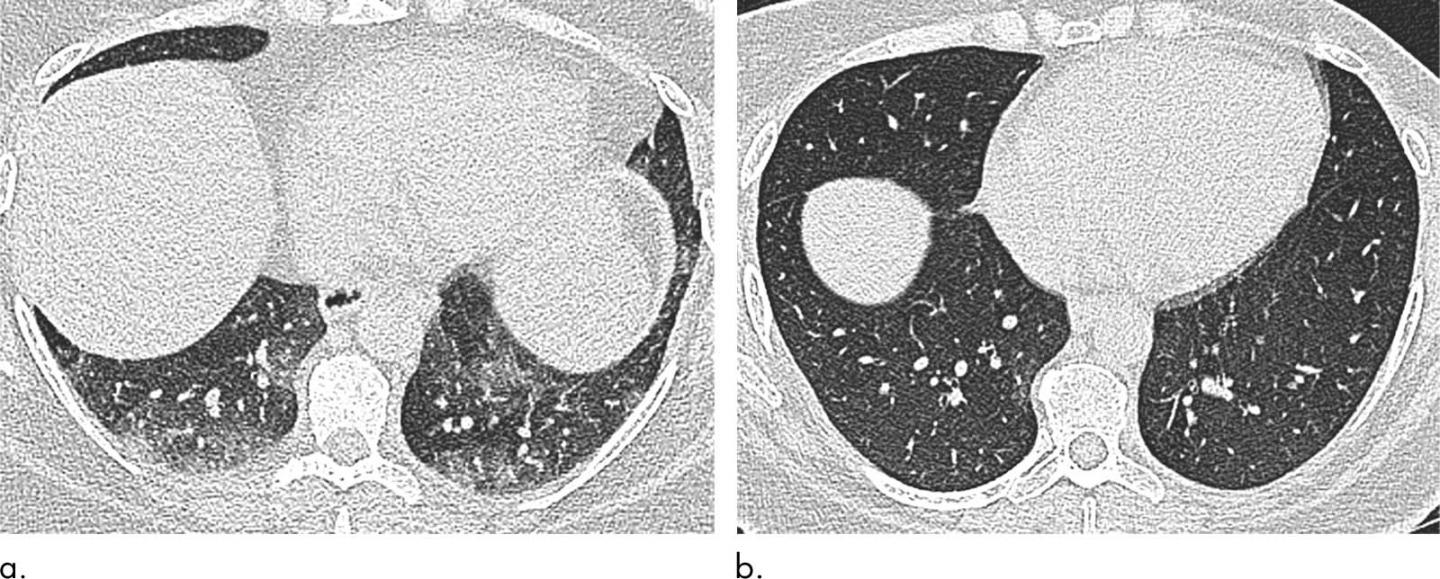

The researchers used CT to measure the size and shape of the trachea and assess air trapping, a phenomenon in which excess air remains in the lungs after exhaling, resulting in a reduction in lung function. Air trapping is an indirect sign of obstruction in the small airways of the lung.

When the researchers compared results at baseline and six months after bariatric surgery, they found that surgery and weight loss were associated with morphological, or structural, changes to the lung and trachea.

Post-surgery CT showed reductions in air trapping and a lower incidence of tracheal collapse. Change in the extent of CT air trapping was the strongest predictor of improvement in dyspnea, or shortness of breath.

"For the first time, this study has demonstrated changes in the CT morphology of large and small airways that improve when individuals lose weight," Dr. Copley said. "These features correlate with an improvement in patient symptoms."

The results suggest that there may be a reversible element of small airway inflammation related to obesity and that reversal of this inflammation correlates with improvement in symptoms. The findings also point to CT as a potential marker of this inflammation.